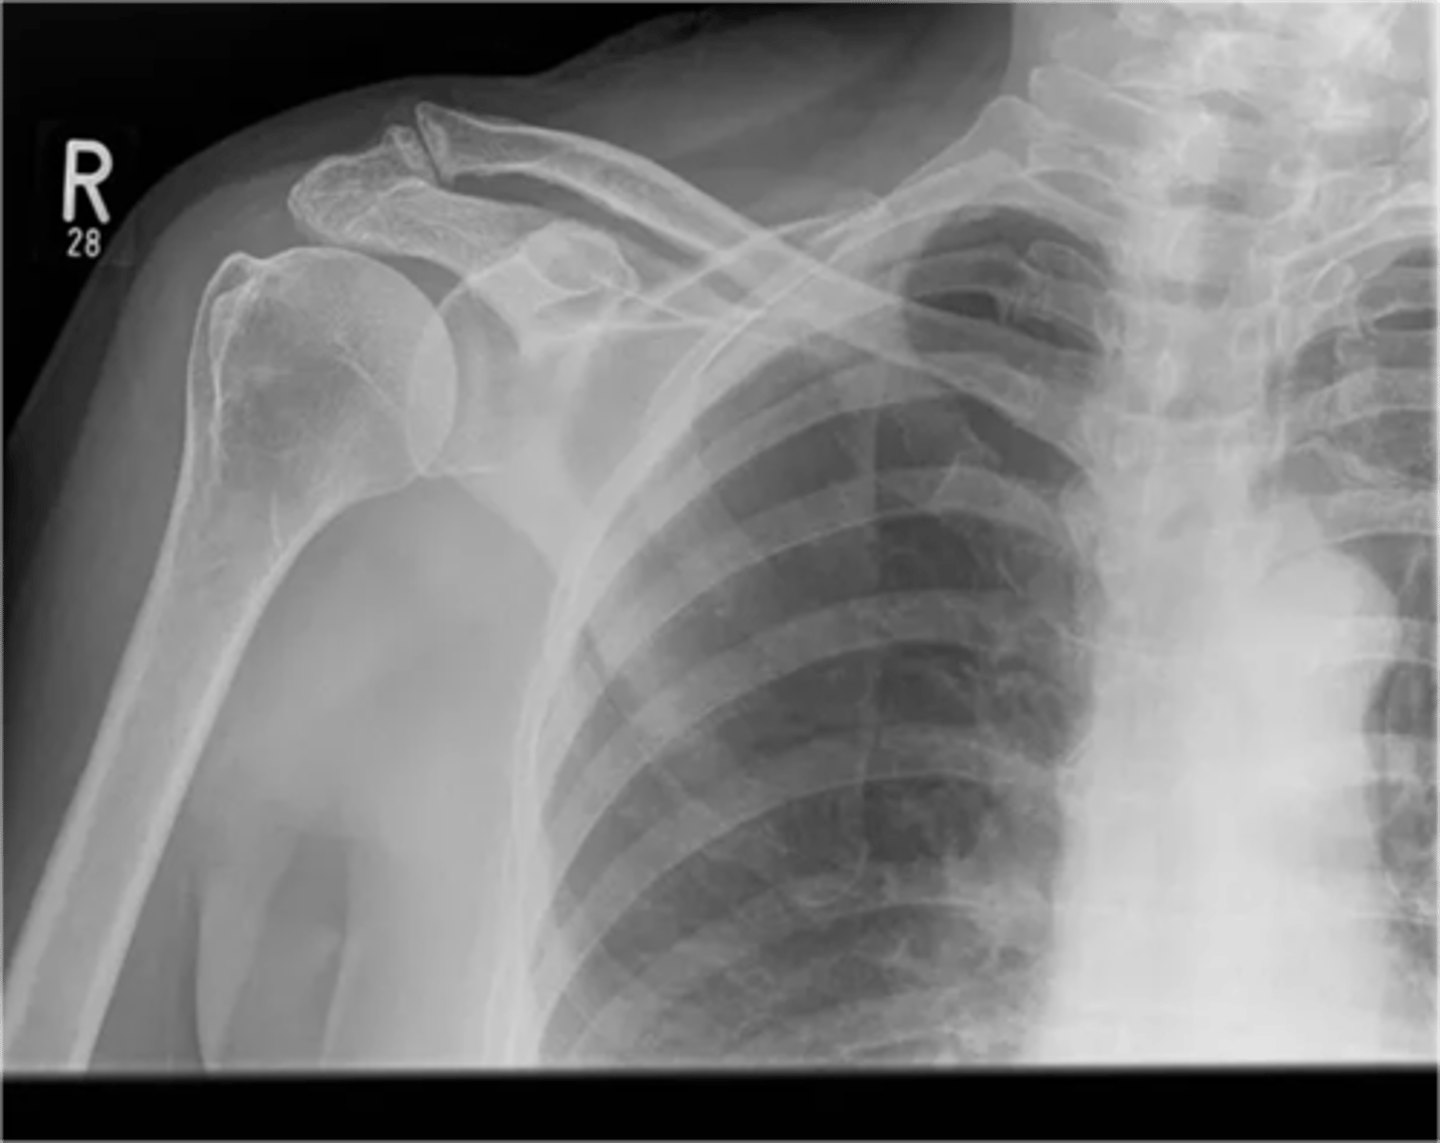

Grade II -- normal to palpate a little step-up deformity at this time, but does NOT require surgical repair

Which grade ACJ separation would this be considered?

Grade III -- acromion migrated WELL below the clavicle and the AC and CC ligaments are both torn